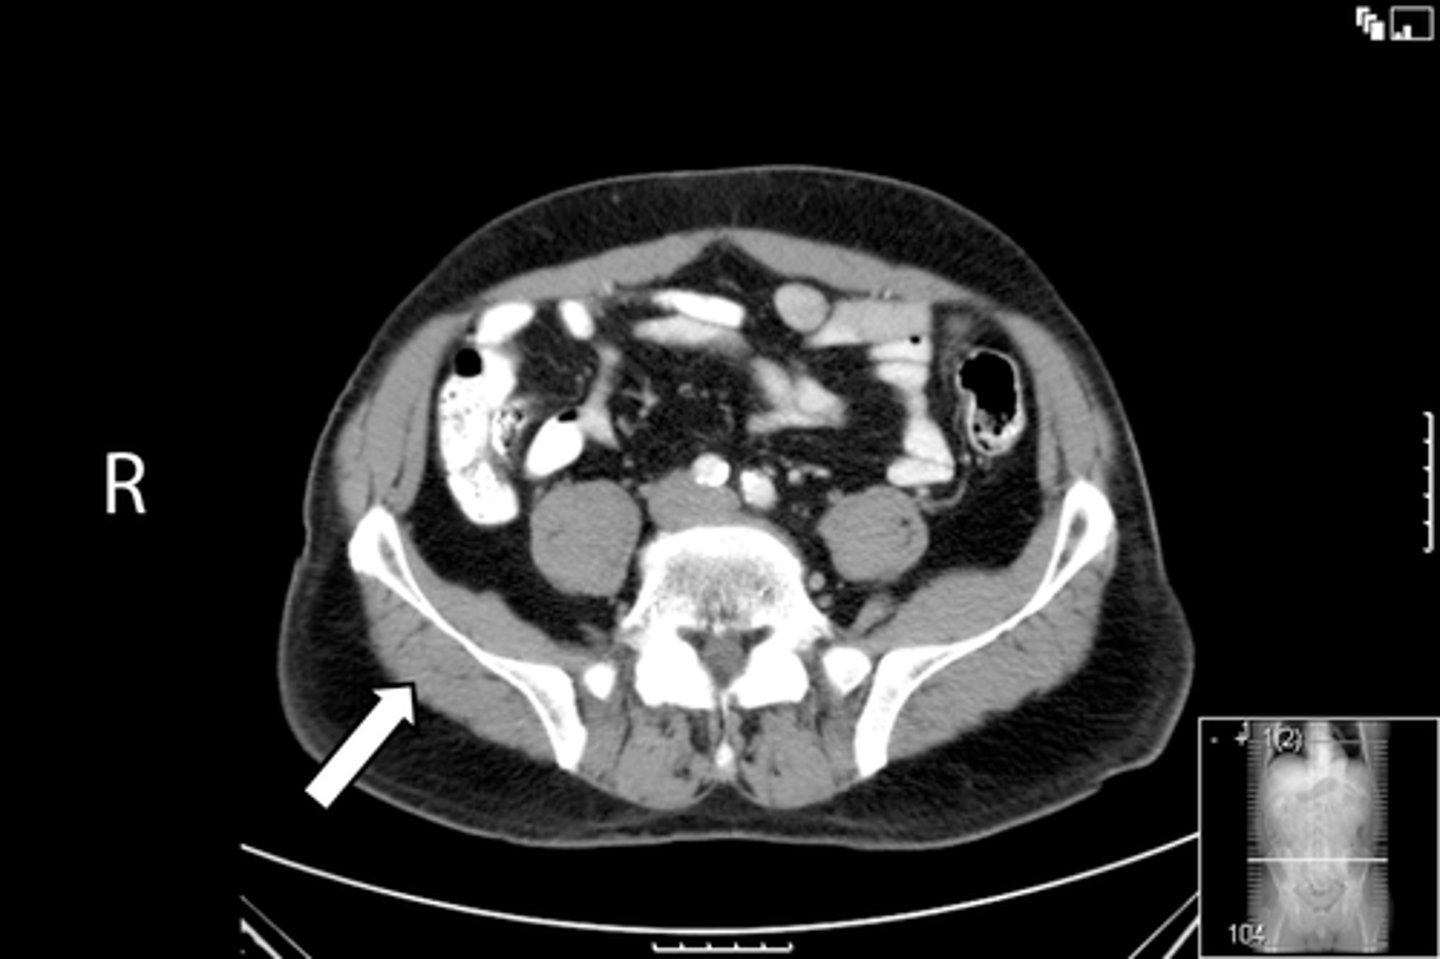

Axial male pelvis CT

What is the image?

78

New cards

Descending colon/sigmoid colon juncture

What is indicated in the image?

<p>What is indicated in the image?</p>

79

L external iliac artery

80

L gluteus muscle

81

L iliopsoas muscle

82

L internal iliac artery

83

Posterior aspect of L iliac bone

84

L sacroiliac joint

85

R common iliac artery

86

R gluteus muscle

87

R iliacus muscle

88

Posterior aspect of right iliac bone

89

R psoas muscle

90

R sacroiliac joint

91

R and L rectus abdominis